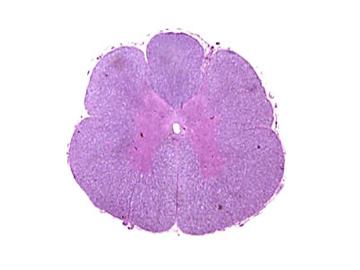

médula espinal